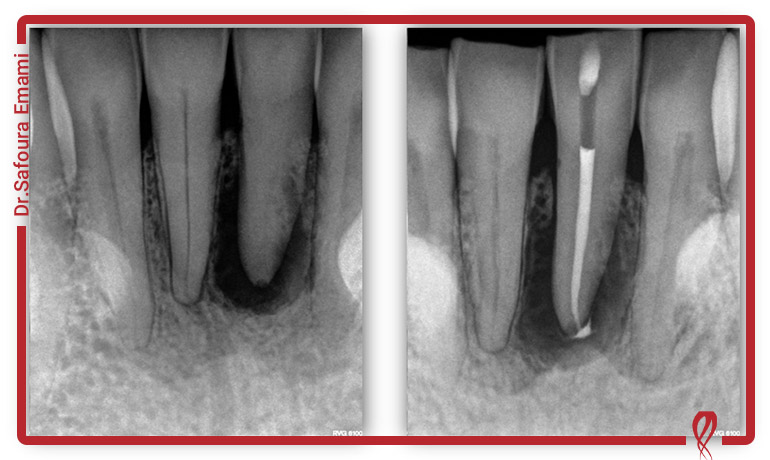

تشخیص به موقع مشکلات دهانی در این بیماری از وظایف مهم دندانپزشک است. در طول درمان لازم است حفره دهان سالم مانده و لازم است عفونتهای حاد دندان و لثه به موقع درمان شود. متخصصین در مراکز مجهز، آموزشهای لازم برای مراقبت از بیمار مبتلا به ایدز را دریافت کردهاند.

خدمات دندانپزشکی شامل برش بافت و خونریزی است، اما خوشبختانه تا به امروز موردی از ابتلا به بیماری ایدز در درمانهای دندانپزشکی گزارش نشده است. در حال حاضر استریل لوازم و وسایل دندانپزشکی، نگرانیها بابت دریافت خدمات دندانپزشکی را از بین برده است. همچنین اگر فرد مبتلا به ویروس HIV، بیماری خود را گزارش دهد، به مراکز مجهز ارجاع داده شده و این مراکز موظف هستند از لوازم یک بار مصرف برای درمان استفاده کنند.